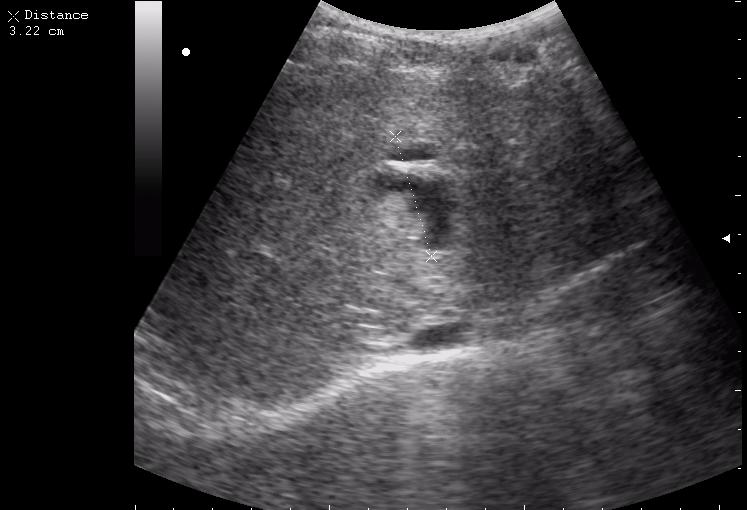

конец рабочего дня тоже "порадовал". Травма об руль велосипеда.

30 мин. после травмы

12-перстная, несмотря на свой пугающий вид, целая

По поводу "разможжения" ткани паренхиматозного органа при травме. Скорее всего-это участки попитывания кровью,т.н. имбибиция.